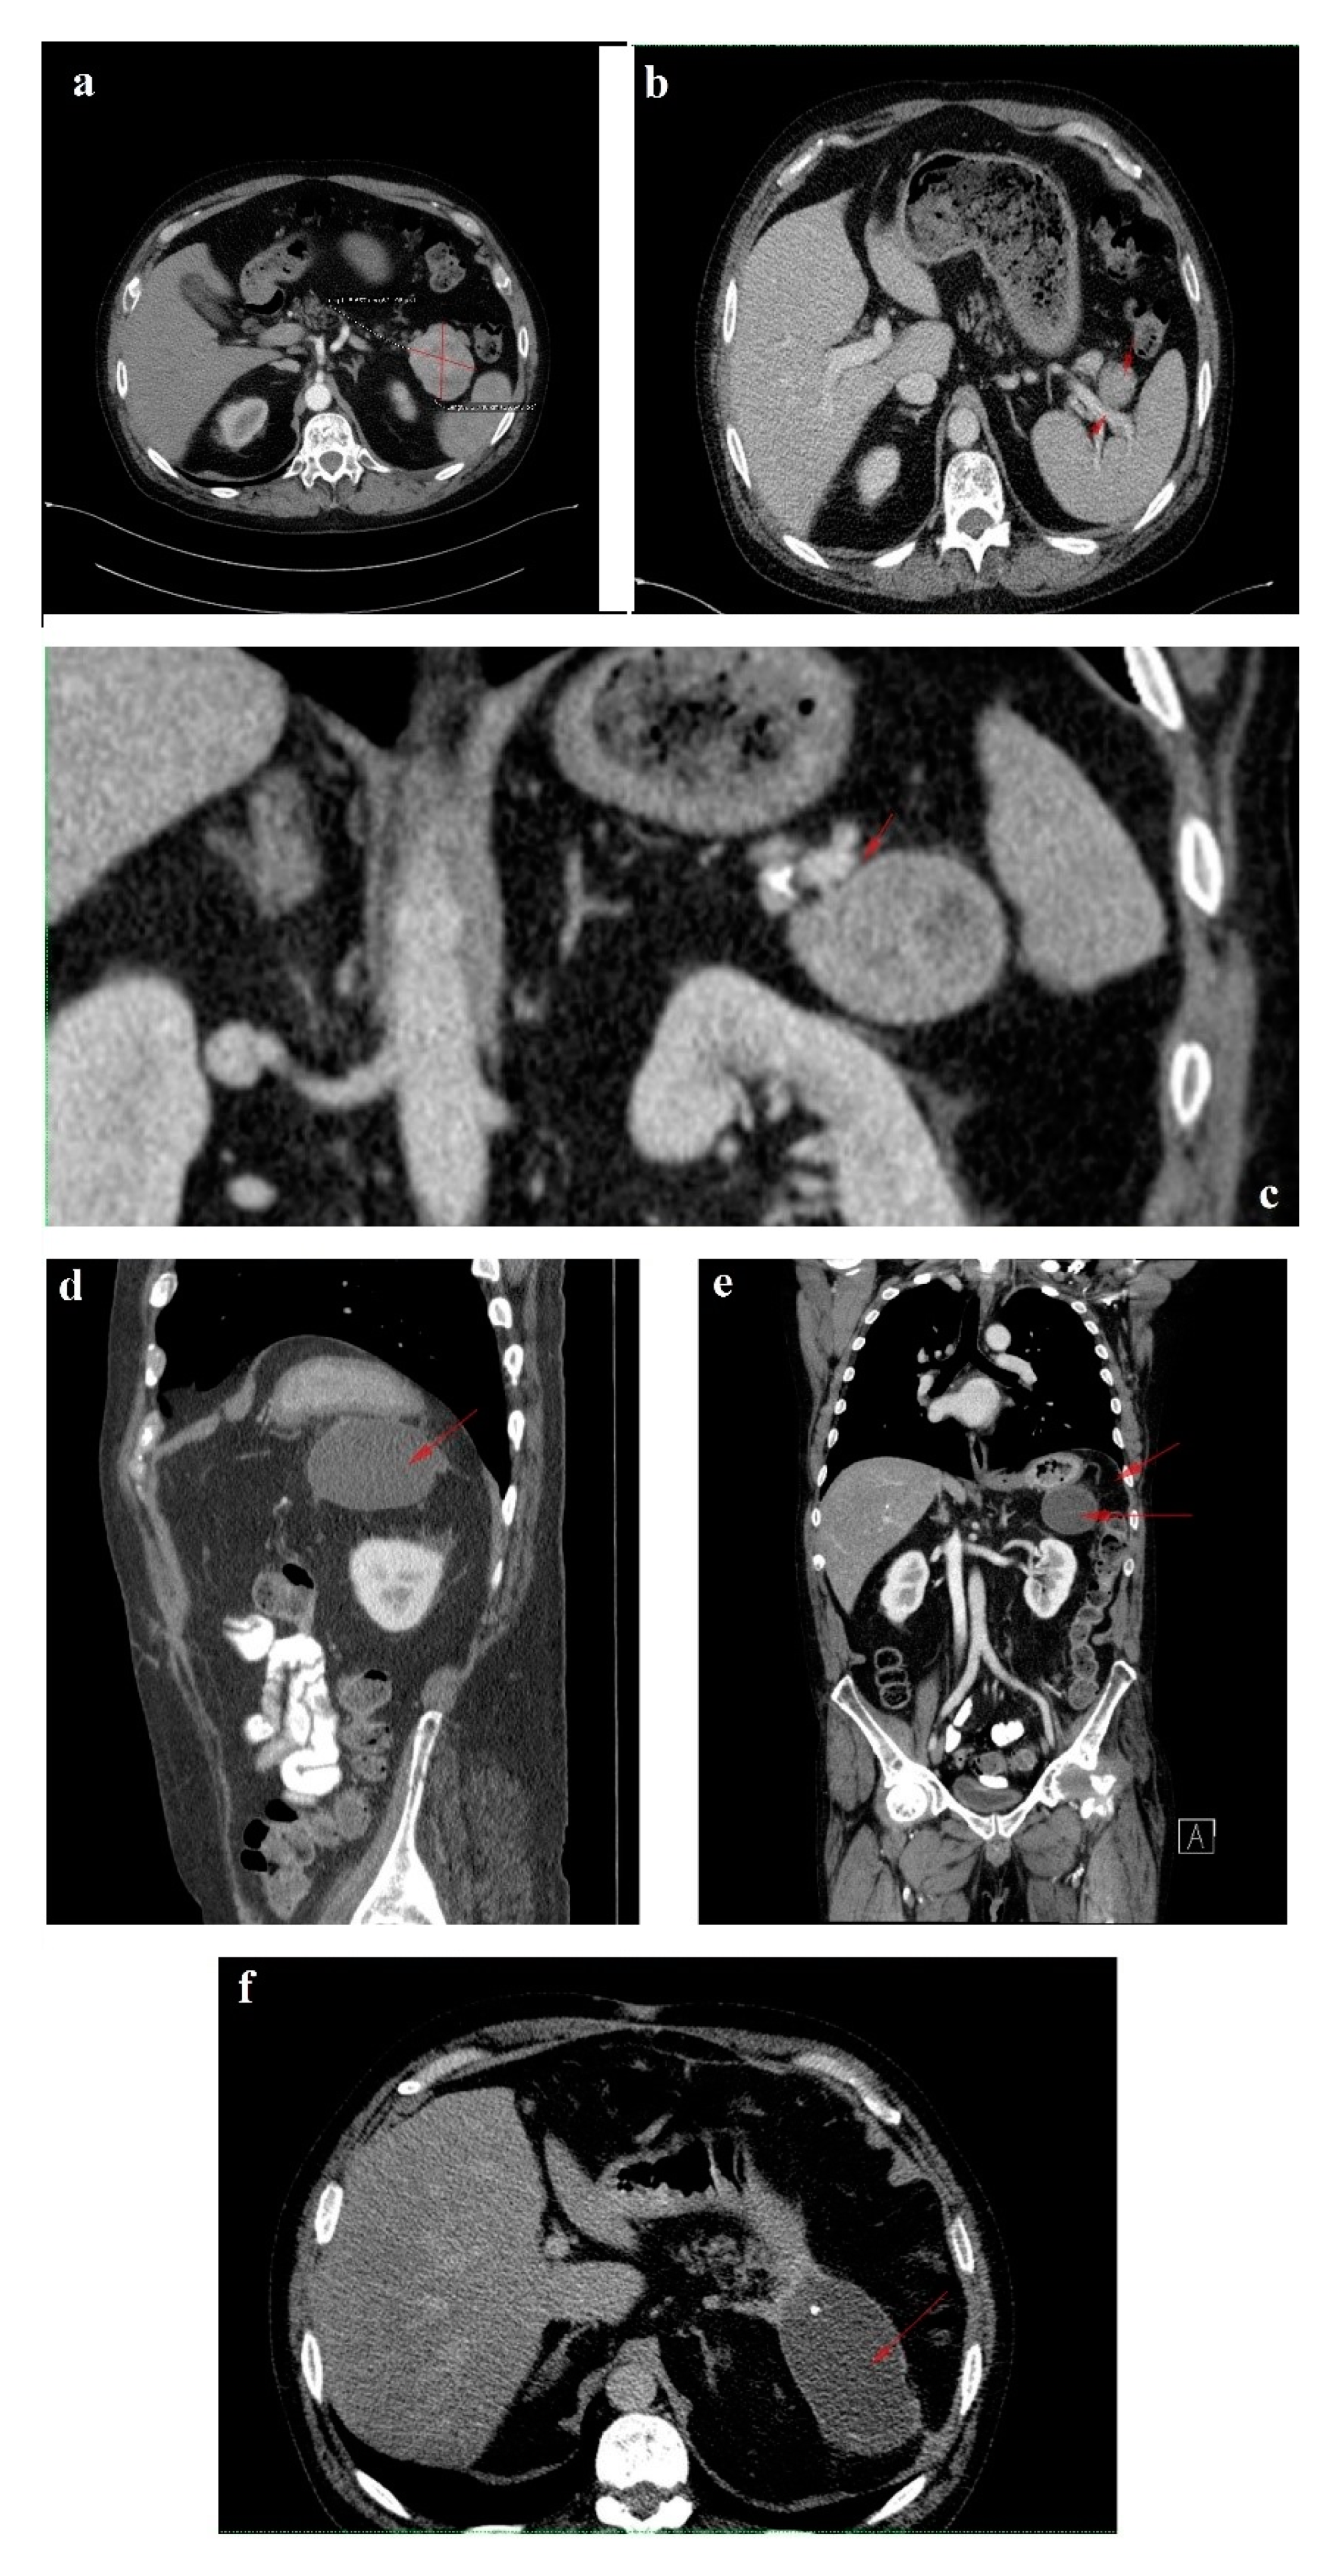

Figure 2. (a) Left (L) pertrochanteric fragility fracture; (b,c) Gamma nail osteosynthesis; (d) Femoral head osteonecrosis and cut-out complication; (e) Girdlestone resection arthroplasty.

Unfortunately, in October 2017, the patient fell from standing height and suffered a left pertrochanteric comminuted fragility fracture, and osteosynthesis with gamma nail was performed (Figure 2a–c). The immediate evolution was further complicated by wound dehiscence that called for surgical debridement.

In the spring of 2019, the patient maintained clinical remission of the hormonal syndrome and stable disease imaging. Nonetheless, he presented with a purulent cutaneous fistula at the incision level performed for the pertrochanteric fracture. Following orthopedic and biological evaluations, hip radiography and bacteriological examination, necrosis of the femoral head with a “cut-out” phenomenon was diagnosed as a possible complication of the previous glucocorticoid therapy (Figure 2d). Vancomycin and clindamycin-sensitive Staphylococcus epidermidis and Klebsiella were identified in the fistula secretion and treated with antibiotics. Due to this septic situation, the ablation of the implant and the surgical sanitation of the hip septic foci were mandatory. Meanwhile, the patient maintained spontaneous INR values of 3–5, which was difficult to manage in the perioperative septic setting. Lastly, the ablation of the osteosynthesis material and the Girdlestone-type femoral head resection arthroplasty were performed (Figure 2e). No intra- or periarticular purulent collections were detected intraoperatively. False membranes from inside the implant were collected and the same staphylococcus epidermidis was identified.